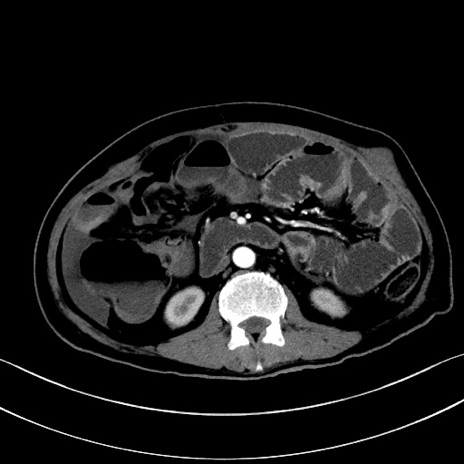

冠状断像

【症例】60歳代男性

【主訴】嘔吐

【現病歴】胃癌にて胃全摘後。食思不振が悪化し、夜中に嘔吐することがある。

【既往歴】胃癌、胃全摘、脾摘、胆摘後

【データ】WBC 5900、CRP 10.56